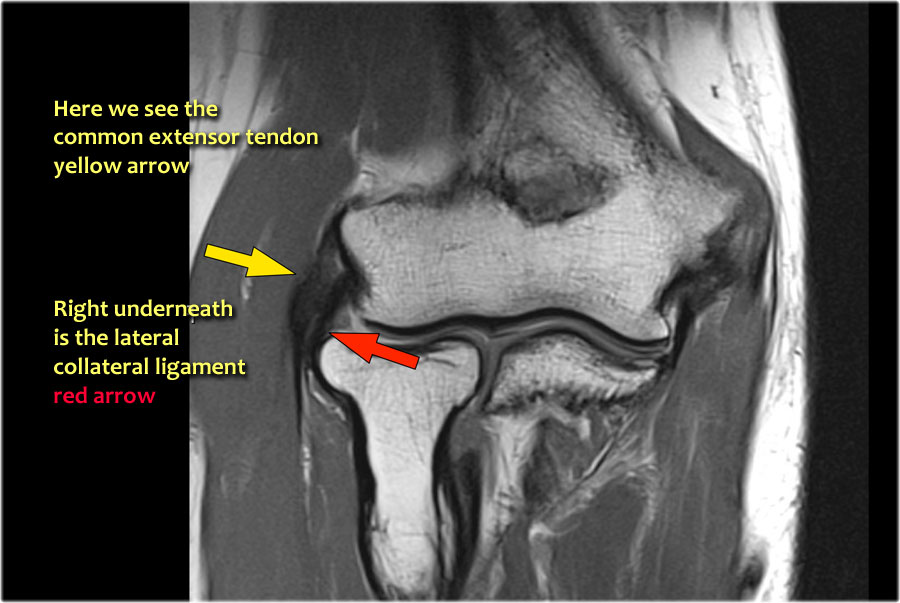

Common extensor tendon

Originates at the lateral epicondyle.

Dây chằng bên ngoài

Xuất phát ngay bên dưới điểm bám của gân duỗi chung.

Dây chằng bên trụ ngoài

Đây là một thuật ngữ có phần khó hiểu dùng để chỉ một gân cũng xuất phát ngay bên dưới gân duỗi chung. Nó vòng xuống phía sau chỏm quay và bám vào vùng xương trụ được gọi là mào cơ ngửa – xem hình ảnh mặt bên.

Khi bạn tìm kiếm dây chằng bên quay, trước tiên hãy cố gắng xác định gân duỗi chung, vì ngay bên dưới nó bạn sẽ tìm thấy dây chằng bên quay (mũi tên vàng).

Khi bạn di chuyển về phía sau hơn, bạn sẽ thấy LUCL – dây chằng bên trụ ngoài, quét ra phía sau chỏm quay (mũi tên trắng).